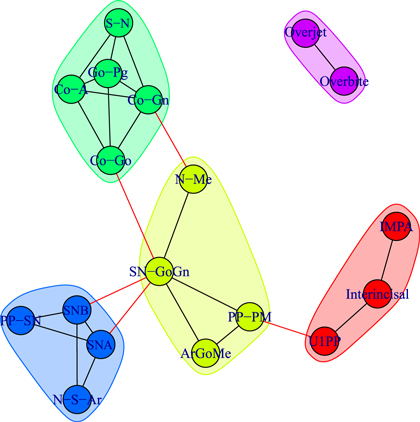

Figure 3 illustrates the correlation network of the cephalometric characteristics of the Class III patients (age 7–13 years) before orthopedic treatment with RME/FM (T1). We see that the network splits into two components: the dentoalveolar adaptive variables (figure 3, top) and the skeletal variables (figure 3, bottom). Moreover, the skeletal horizontal variables (figure 3, bottom right) and skeletal vertical variables (figure 3, bottom left) are loosely connected by a link among the gonial angle (ArGoMe) and the distance between Gonion and Pogonion points (Go-Pg).

Figure 3. Network analysis of cephalometric features of the Class III patients (T1, 7–13 years of age) before RME/facemask treatment. The dashed lines indicate negative correlations. In the upper part of the drawing are shown the dentoalveolar adaptive nodes that have been released from the rest of the network. The triangle formed by SN-GoGn, ArGoMe, and PP-PM variables comprises the parameters of maxillomandibular divergence. In the lower right part of the drawing is the sub-network of craniofacial skeletal features. The graphs shown here and in subsequent figures were produced using yEd Graph Editor by www.yworks.com.

Standard image High-resolution imageThe same patients were re-assessed at the end of the RME/FM therapy, followed by a second phase of treatment with fixed appliances (T2; figure 4). Network analysis show a more interlinked structure between skeletal and dentoalveolar adaptive nodes and the appearance of a strong correlation among the overbite and overjet variables.

Figure 4. Network analysis of the same Class III patients re-evaluated after RME/FM therapy followed later by fixed appliances (T2, 11–18 years of age).

Standard image High-resolution imageFinally, figure 5 illustrates the correlation network of the cephalometric characteristics of the cohort of the untreated Class III controls of 11–18 years of age (U2).

Figure 5. Network analysis of the Class III untreated control subjects (U2, 11–18 years of age).

Standard image High-resolution imageWhile the network of treated patients at the end of RME/FM therapy showed a highly interconnected structure between dentoalveolar adaptive and skeletal variables (figure 4), the network of control patients exhibited two separate sub-networks pertaining to skeletal (left) and dentoalveolar (right) adaptive nodes (figure 5). The core of the network of treated patients consisted of a triangle composed by three maxillomandibular divergence variables: SN-GoGN, ArGoMe, and PP-MP. These variables seem to act as a bridge between skeletal features of Class III malocclusion and the dentoalveolar adaptive components of the craniofacial system.

We detect modules by applying the walktrap algorithm [42] on the complete graphs corresponding to consider all the possible edges weighted with their correlation rij; in particular, we use the igraph [44] implementation of the function walktrap.community of R [45]. To compare the results with the empirical outcomes of section 3.1, we show in all the pictures only links with a correlation correlation  and only nodes connected by such links. The analysis of the modules shows interesting differences among the three groups of patients: in fact, the modules characterising the networks of the patients before control (T1) and the untreated control patients (U2) share a similar structure (see figures 6 and 8) with three modules composed by analogous nodes. In fact, like in figure 3, the modules of T1 shown in figure 6 correspond to dentoalveolar adaptive nodes (top right of the picture), to skeletal horizontal nodes (bottom right of the picture) and skeletal vertical nodes (left of the picture); a similar correspondence exists among figures 5 and 8. Notice that for both T1 and U2 the modules are either separated or linked by negative links, indicating that such groups of nodes work as separate, non interacting, oro-facial modules. On the other hand, the network of treated patients (T2, figure 7) shows more modules ; apart to the new (respect to T1 and U2) isolated community formed by overjet and overbite (whose correlation is due to the successful action of the braces), the remaining communities are much more interlinked, possibly hinting a harmonization of the orofacial modules that start working together thanks to the orthodontic correction.

and only nodes connected by such links. The analysis of the modules shows interesting differences among the three groups of patients: in fact, the modules characterising the networks of the patients before control (T1) and the untreated control patients (U2) share a similar structure (see figures 6 and 8) with three modules composed by analogous nodes. In fact, like in figure 3, the modules of T1 shown in figure 6 correspond to dentoalveolar adaptive nodes (top right of the picture), to skeletal horizontal nodes (bottom right of the picture) and skeletal vertical nodes (left of the picture); a similar correspondence exists among figures 5 and 8. Notice that for both T1 and U2 the modules are either separated or linked by negative links, indicating that such groups of nodes work as separate, non interacting, oro-facial modules. On the other hand, the network of treated patients (T2, figure 7) shows more modules ; apart to the new (respect to T1 and U2) isolated community formed by overjet and overbite (whose correlation is due to the successful action of the braces), the remaining communities are much more interlinked, possibly hinting a harmonization of the orofacial modules that start working together thanks to the orthodontic correction.

Figure 6. Module repartition of the Class III patients before treatment (T1). The detected modules correspond to dentoalveolar adaptive nodes (top right—red), to skeletal horizontal nodes (bottom right—green) and skeletal vertical nodes (left—blue).